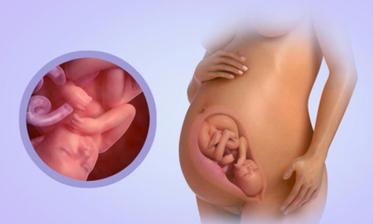

23.5. pro průkazku + odběr krve + utz 11+0 mimisek 4,2cm